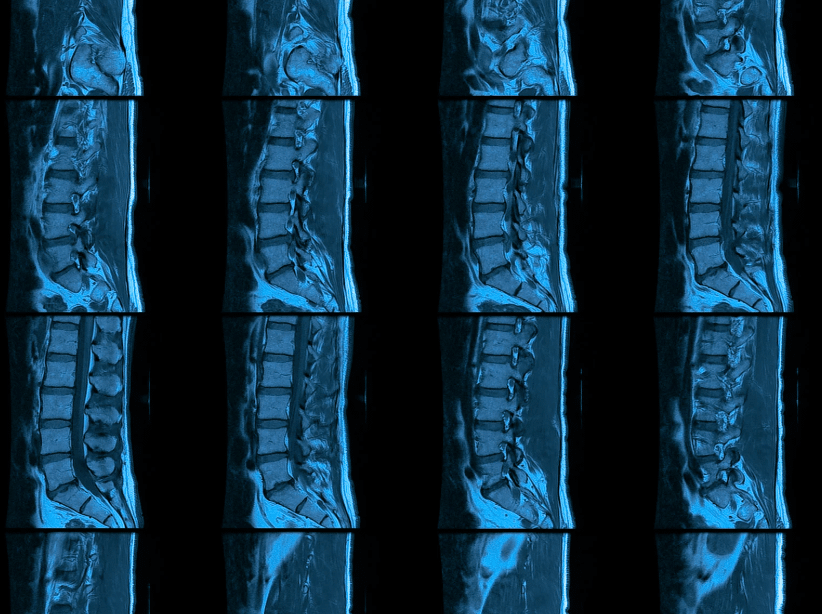

En el estudio de la columna vertebral, este examen permite visualizar con gran precisión:

- Vértebras (huesos de la columna).

- Discos intervertebrales (los “amortiguadores” entre vértebras).

- Médula espinal y raíces nerviosas.

- Músculos, ligamentos y tejidos blandos asociados.

Gracias a su nivel de detalle, la resonancia de columna ayuda a identificar lesiones o alteraciones que no se detectan fácilmente con otros estudios.

Ocurren cuando un disco intervertebral se desplaza o rompe, presionando los nervios y generando dolor, hormigueo o debilidad. La resonancia muestra el nivel, magnitud y el tipo de hernia, información clave para decidir el tratamiento adecuado.

La RM permite identificar si un nervio está comprimido por una vértebra desplazada, un disco inflamado o artrosis. Es clave para evaluar lumbociáticas, cervicalgias irradiadas o dolores persistentes.

Tras una caída o accidente, la resonancia puede detectar fisuras, fracturas ocultas o desplazamientos leves que podrían pasar desapercibidos en otros exámenes.

La RM también sirve para evaluar la médula espinal y descartar inflamaciones, tumores, lesiones desmielinizantes o enfermedades degenerativas que afecten la movilidad o la sensibilidad.

Con la edad, los discos y articulaciones de la columna pierden elasticidad. La resonancia puede evidenciar los signos de desgaste y permite planificar terapias que alivien el dolor crónico y mejoren la movilidad.